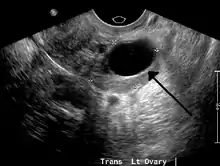

Ovarian cyst

| A simple ovarian cyst of most likely follicular origin | |

Ovarian cysts are usually diagnosed by ultrasound, CT scan, or MRI, and correlated with clinical presentation and endocrinologic tests as appropriate.